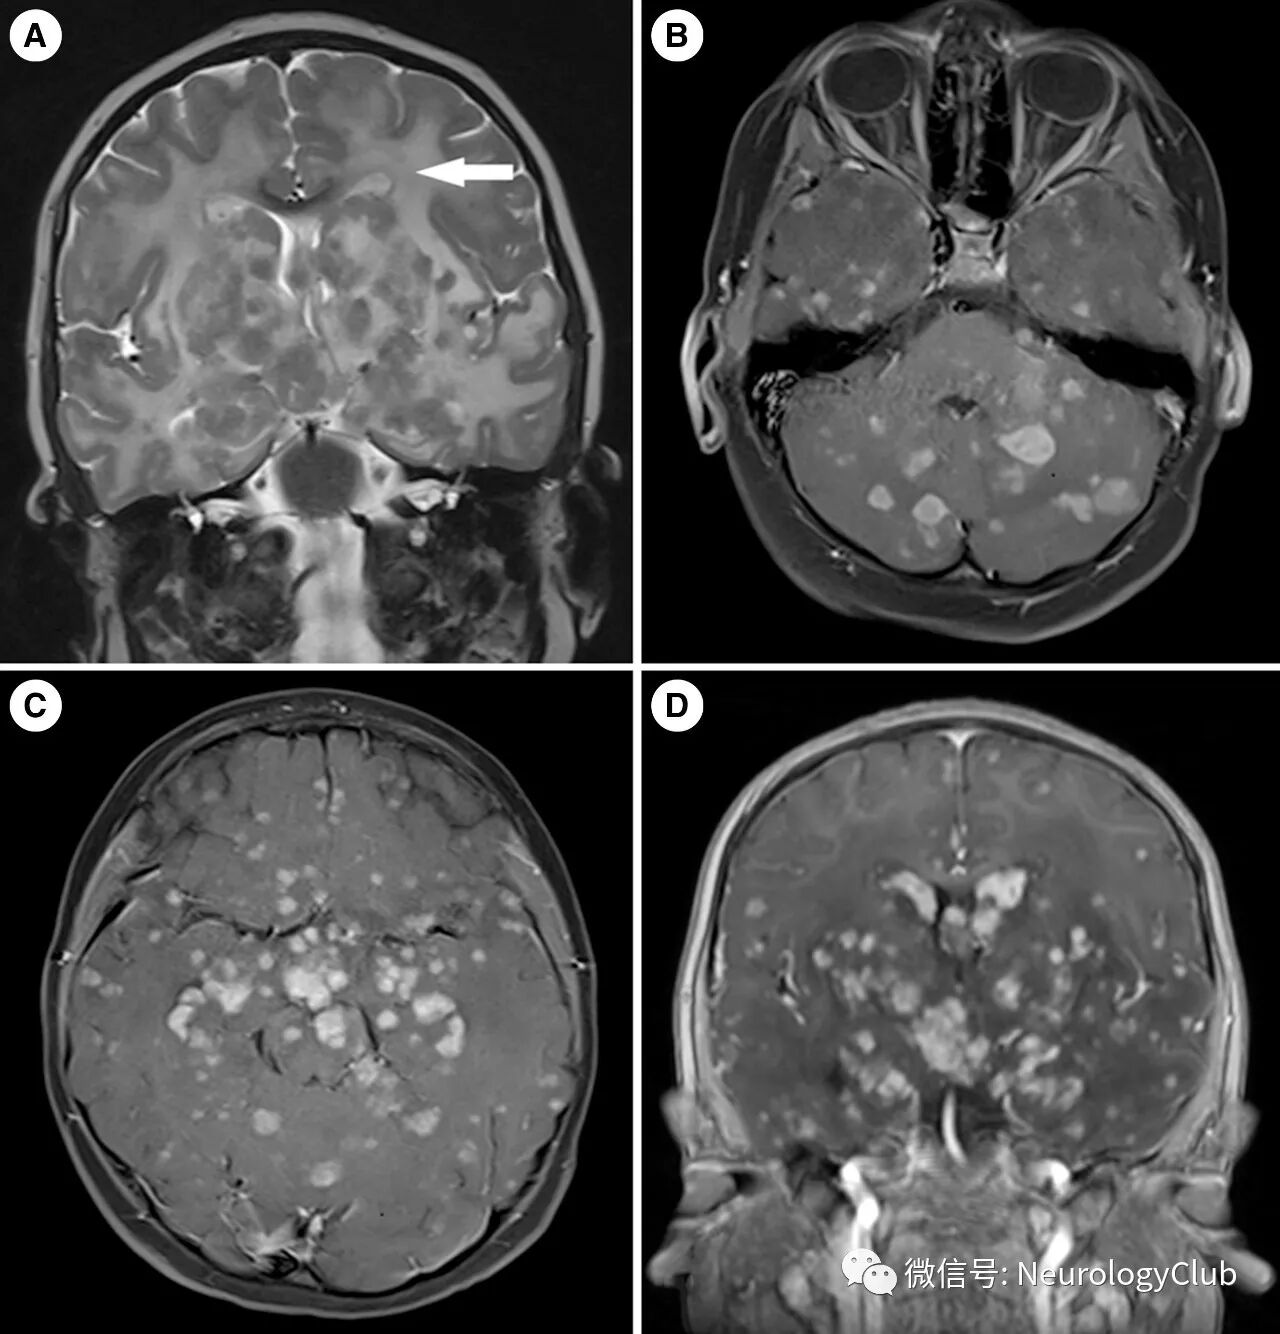

头颅MRI可见垂体柄增粗伴局限性下丘脑和松果体病变。此外T1WI上垂体后叶生理性高信号消失(图1)。FLAIR和T2WI可见脑白质广泛高信号和多发结节样病灶。增强后结节样病灶明显强化(图2)。未见骨性破坏。全身其他脏器影像学检查未发现异常。

(图2:A:T2WI可见双侧大脑半球弥漫高信号白质病变;B-D:增强T1WI可见脑实质内多发肉芽肿性强化病灶)

颅内LCH的典型MRI表现包括垂体柄增粗,有时可见垂体和下丘脑区域占位性病变。此外,肿瘤样病灶也可见于脑膜,脉络丛或松果体。第二常见的MRI表现为小脑灰质T1WI低或高信号改变,称为“放射学神经退行性变”。在某些重度残疾的儿童患者中,T2WI上可见小脑和大脑片状至融合的白质病变。非常少的病例报道提及脑实质肉芽肿性病变。本例患者的MRI改变较为特殊,表现为多发的幕上和幕下结节样病灶伴弥漫白质病变,故鉴别诊断较多,包括生殖细胞肿瘤,结节病,脑转移瘤和感染性疾病,扩大了中枢神经系统LCH的影像学类型。